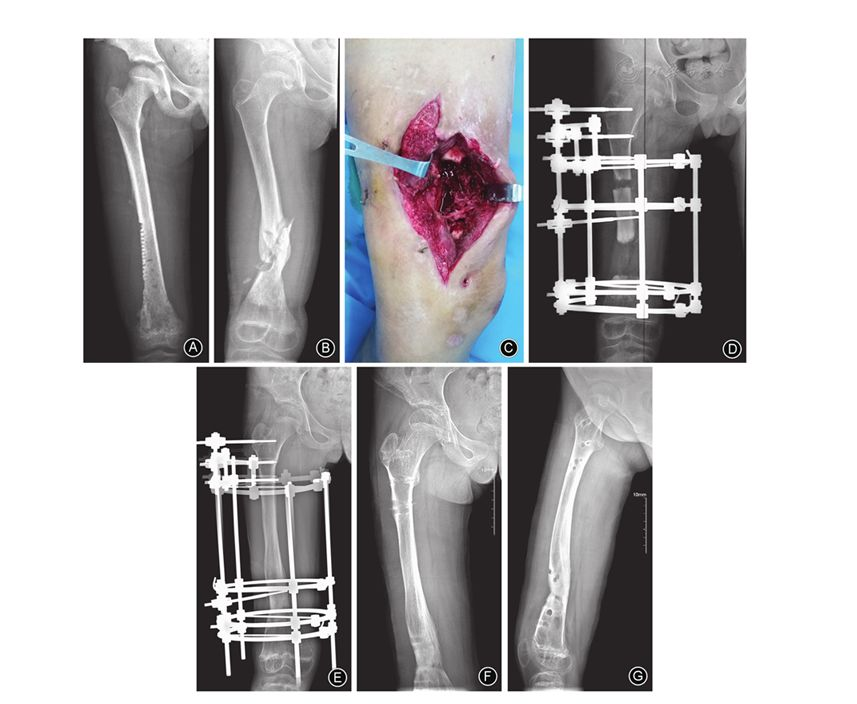

图1 女,9岁,右大腿远端肿痛、局部皮温升高2个月 A 术前股骨正位X线片示右股骨骨髓炎 B 行右股骨钻孔、置管冲洗引流1个月,股骨正位X线片示股骨中下段病理性骨折 C 行清创、死骨清除并植骨 D Ilizarov外固定架固定术后股骨正位X线片示骨缺损约13.5 cm E 术后18.5个月,股骨正位X线片示骨折断端愈合良好,延长骨段矿化完全 F,G 拆除外固定架后2个月,股骨正、侧位X线片示骨搬移断端对合良好,骨性愈合